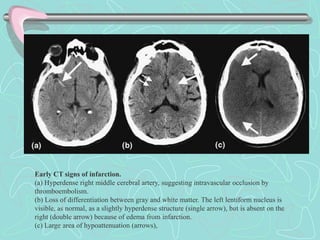

Early CT signs of infarction.

(a) Hyperdense right middle cerebral artery, suggesting intravascular occlusion by

thromboembolism.

(b) Loss of differentiation between gray and white matter. The left lentiform nucleus is

visible, as normal, as a slightly hyperdense structure (single arrow), but is absent on the

right (double arrow) because of edema from infarction.

(c) Large area of hypoattenuation (arrows),